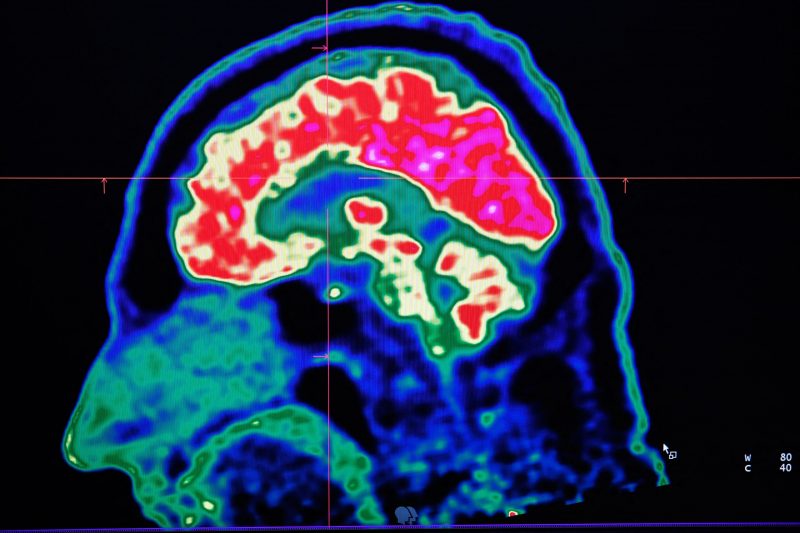

An assistant professor at the University of Connecticut has reportedly found compounds that hold the potential to treat Parkinson’s disease.

On Tuesday, UConn Health, a branch of the university, claimed that Yulan Xiong and her team discovered a key mechanism in Parkinson’s disease research.

Parkinson’s disease is typically caused by a gene mutation called LRRK2. One of the gene’s functions is regulating cell function and transmitting signals.